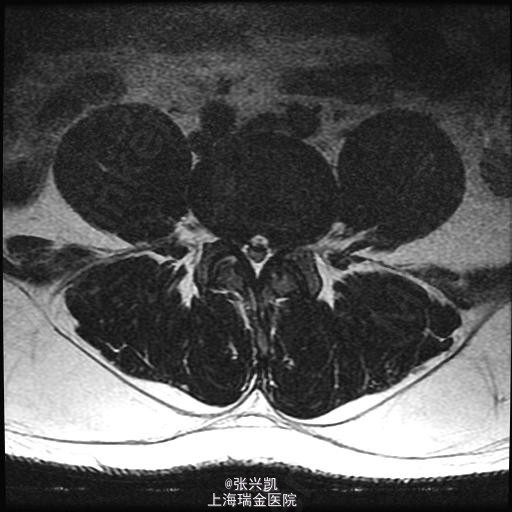

查体:脊柱无侧弯畸形,双上肢感觉活动良好,双侧股四头肌肌力正常,跟、膝腱反射(+),右腿直腿抬高试验45°,左侧70°,右侧足踝外侧麻木感 辅助检查:腰椎MR示:L4-5,L5-S1,椎间盘突出,相应节段伴狭窄,腰椎退行性改变,L5,S1相邻终板变性。

诊断: 1、腰椎椎间盘突出(L4-5,L5-S1) 2、腰椎椎管狭窄(L4-5,L5-S1) 处理: 经后路行L4-5,L5-S1椎管减压,椎间盘摘除,L4-5,L5-S1融合内固定术